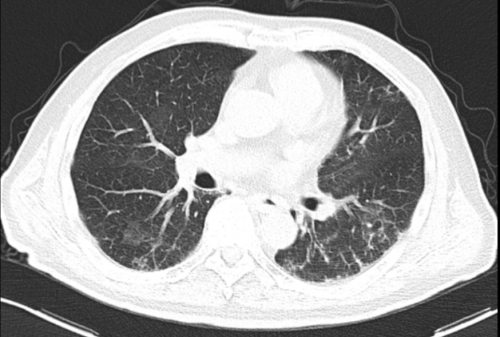

治疗后复查(11-14)

患者复查炎症指标下降,氧和较前好转,肺部CT示双肺渗出性病灶明显吸收,患者从经鼻高流量吸氧过度到鼻导管吸氧,最后能够完全脱离给氧装置,予以出院。